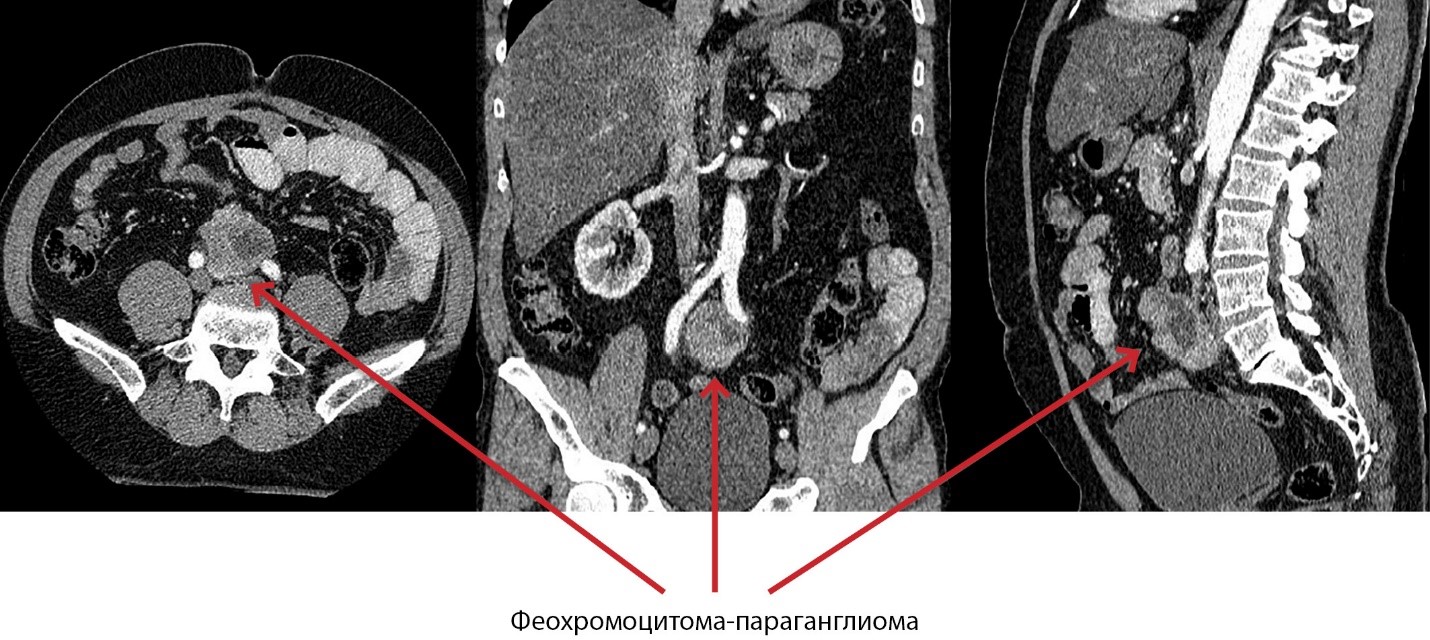

1. Рисунок 1. Фрагменты компьютерной томографии в трех проекциях.

Тема

Тип Исследовательские инструменты

Посмотреть (268KB)